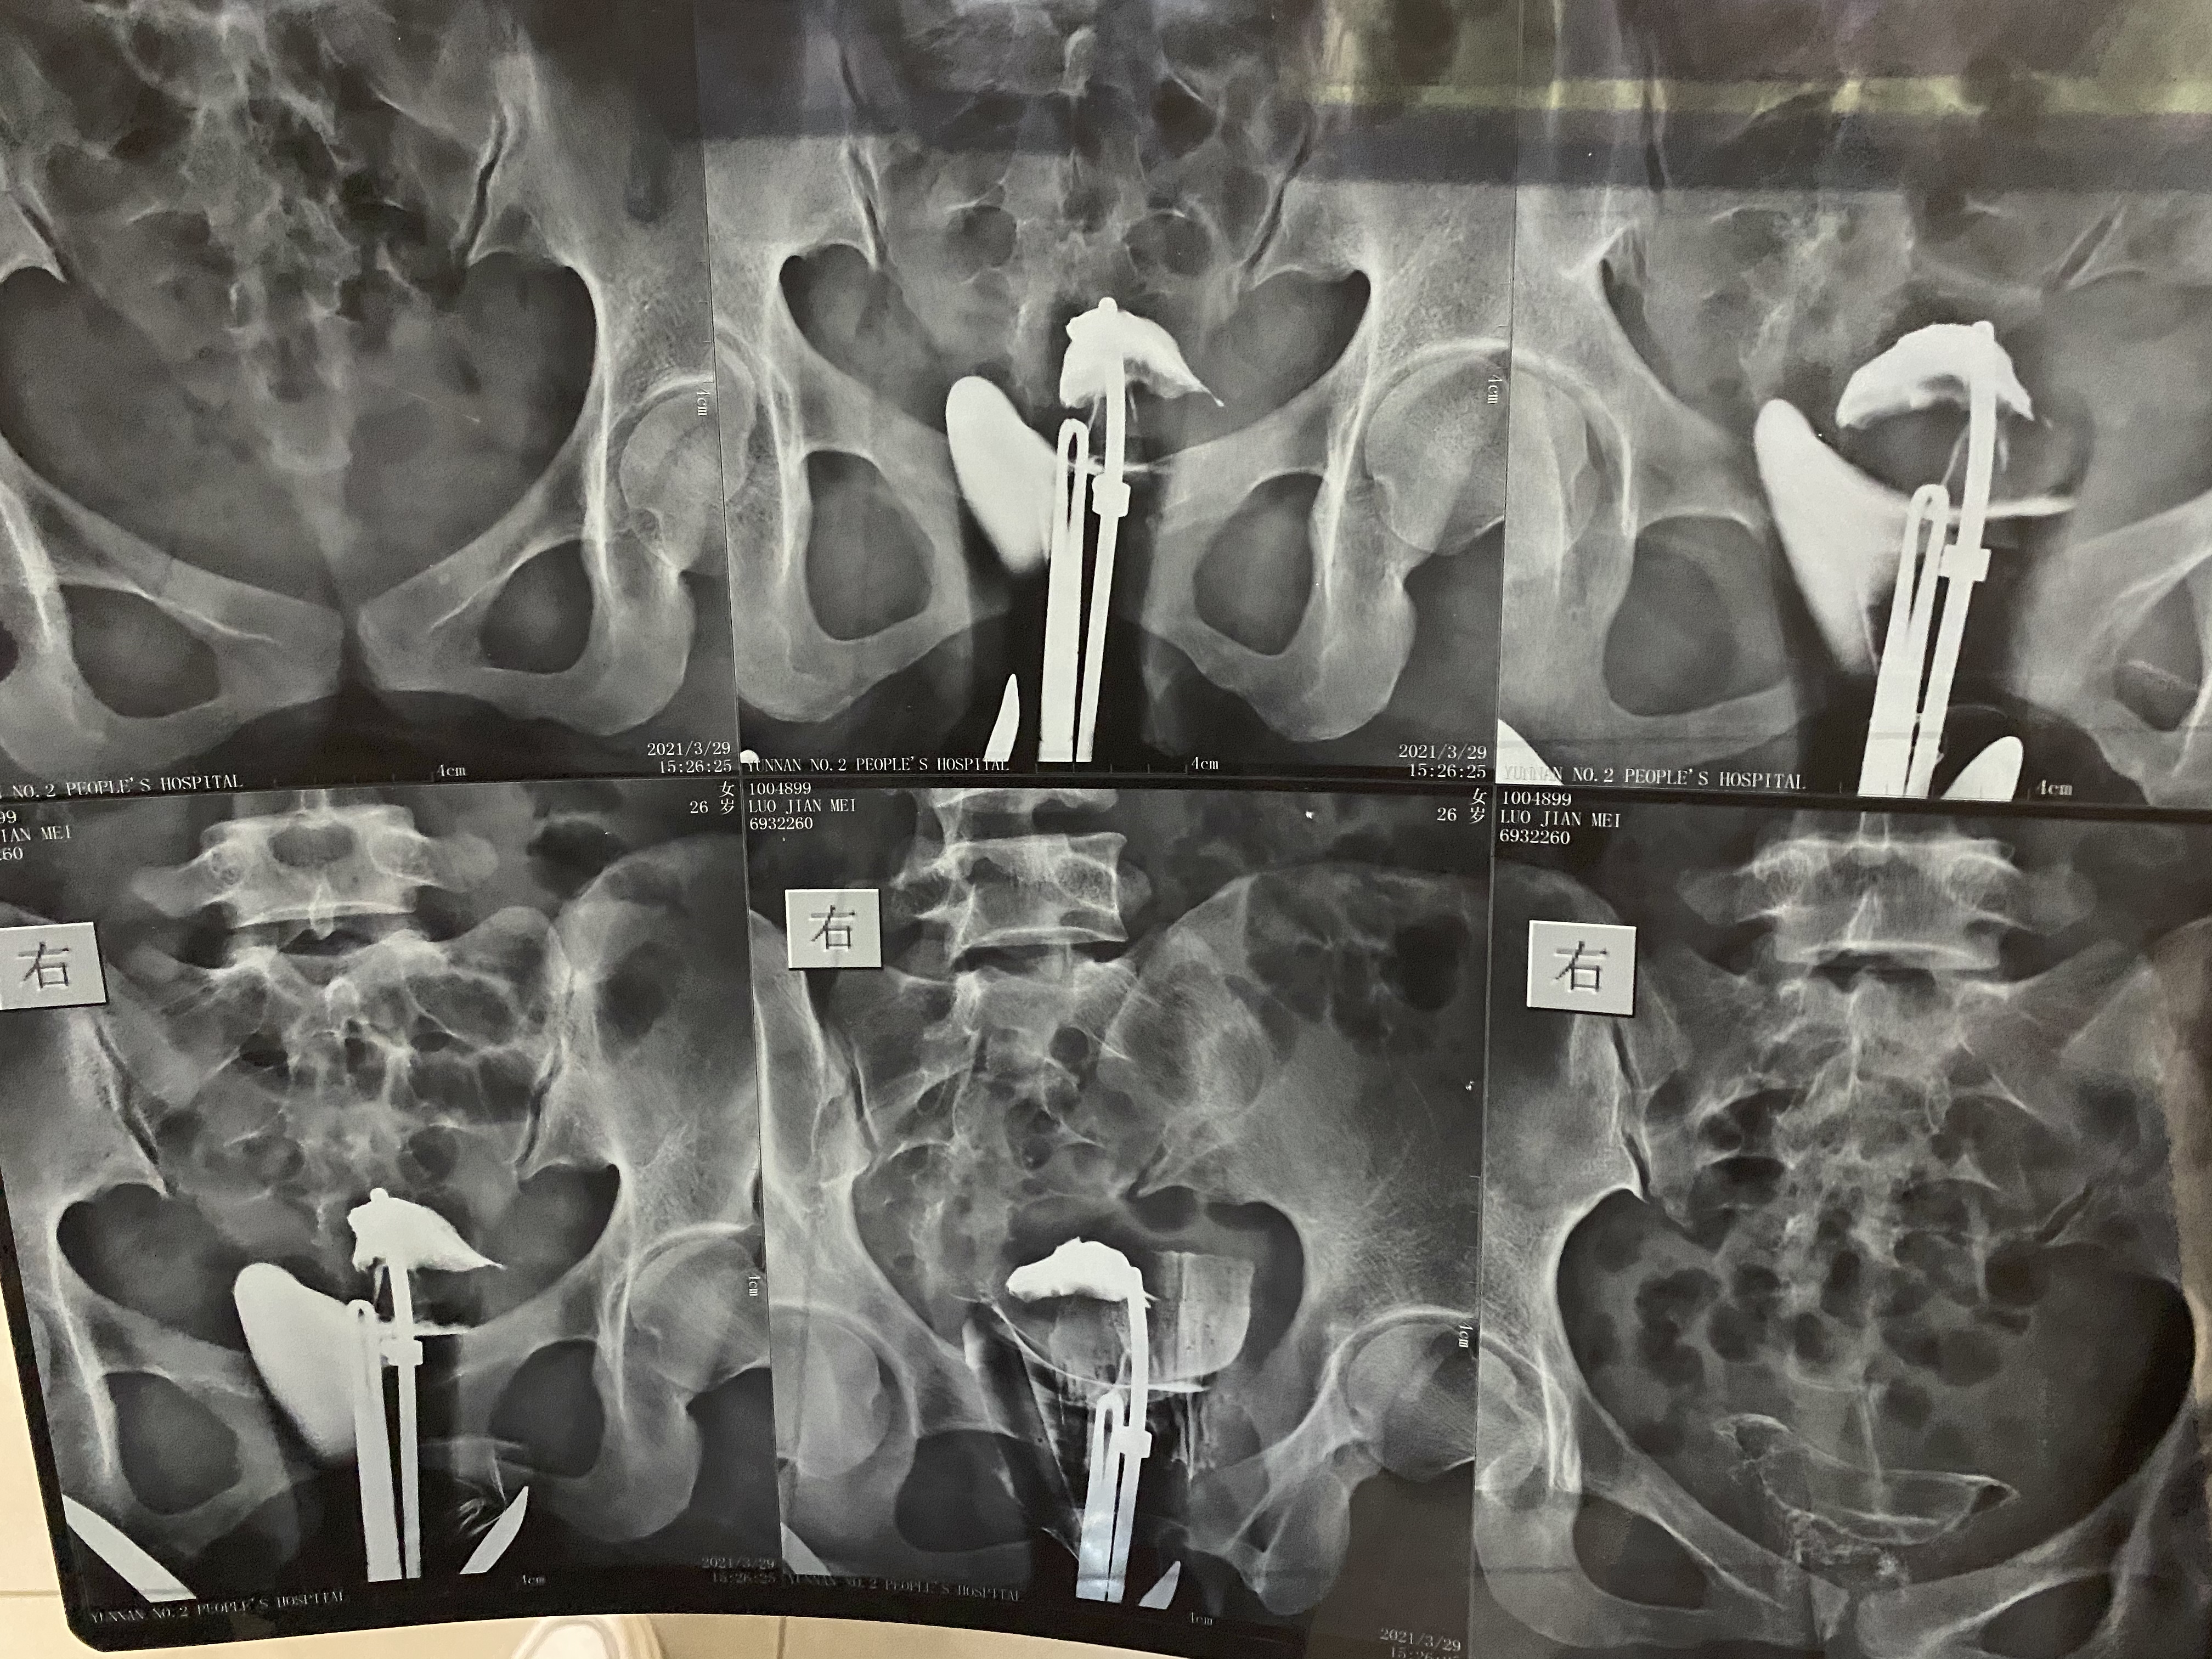

最近做输卵管造影显示输卵管堵塞疏通的概率很低